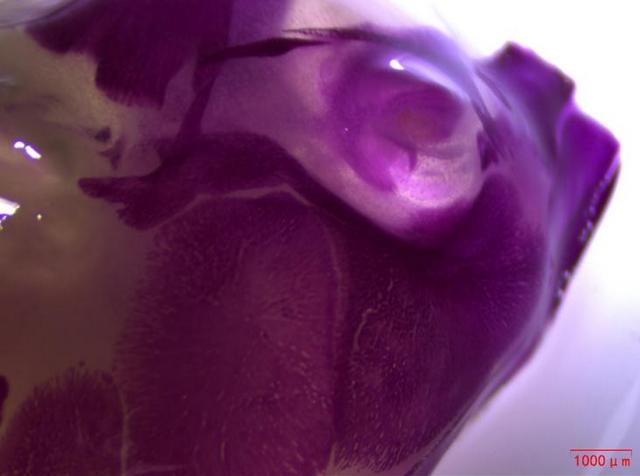

近日,湖南某生物企業(yè)引進(jìn)了Mshot明美生產(chǎn)的體視顯微鏡MZ101,用于觀察小動(dòng)物大體組織,如小鼠幼崽的脊柱和頭部。體視顯微鏡MZ101以成像清晰、超長工作距離和大視野目鏡等顯著特點(diǎn),為生物企業(yè)的科研人員提供了良好的觀察體驗(yàn)。

在動(dòng)物實(shí)驗(yàn)研究領(lǐng)域,對(duì)小動(dòng)物大體組織的清晰觀察至關(guān)重要。明美體視顯微鏡MZ101憑借其高分辨率和優(yōu)異的光學(xué)性能,能夠捕捉到小鼠幼崽脊柱和頭部的每一個(gè)細(xì)節(jié),成像效果令人贊嘆。這無疑為科研人員提供了準(zhǔn)確、可靠的數(shù)據(jù)支持,有助于推動(dòng)藥物研發(fā)進(jìn)程的順利進(jìn)行。